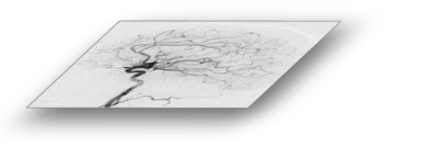

The rapid and accurate direct multi-frame interpolation method for Digital Subtraction Angiography (DSA) images is crucial for reducing radiation and providing real-time assistance to physicians for precise diagnostics and treatment. DSA images contain complex vascular structures and various motions. Applying natural scene Video Frame Interpolation (VFI) methods results in motion artifacts, structural dissipation, and blurriness. Recently, MoSt-DSA has specifically addressed these issues for the first time and achieved SOTA results. However, MoSt-DSA's focus on real-time performance leads to insufficient suppression of high-frequency noise and incomplete filtering of low-frequency noise in the generated images. To address these issues within the same computational time scale, we propose GaraMoSt. Specifically, we optimize the network pipeline with a parallel design and propose a module named MG-MSFE. MG-MSFE extracts frame-relative motion and structural features at various granularities in a fully convolutional parallel manner and supports independent, flexible adjustment of context-aware granularity at different scales, thus enhancing computational efficiency and accuracy. Extensive experiments demonstrate that GaraMoSt achieves the SOTA performance in accuracy, robustness, visual effects, and noise suppression, comprehensively surpassing MoSt-DSA and other natural scene VFI methods. The code and models are available at https://github.com/ZyoungXu/GaraMoSt.